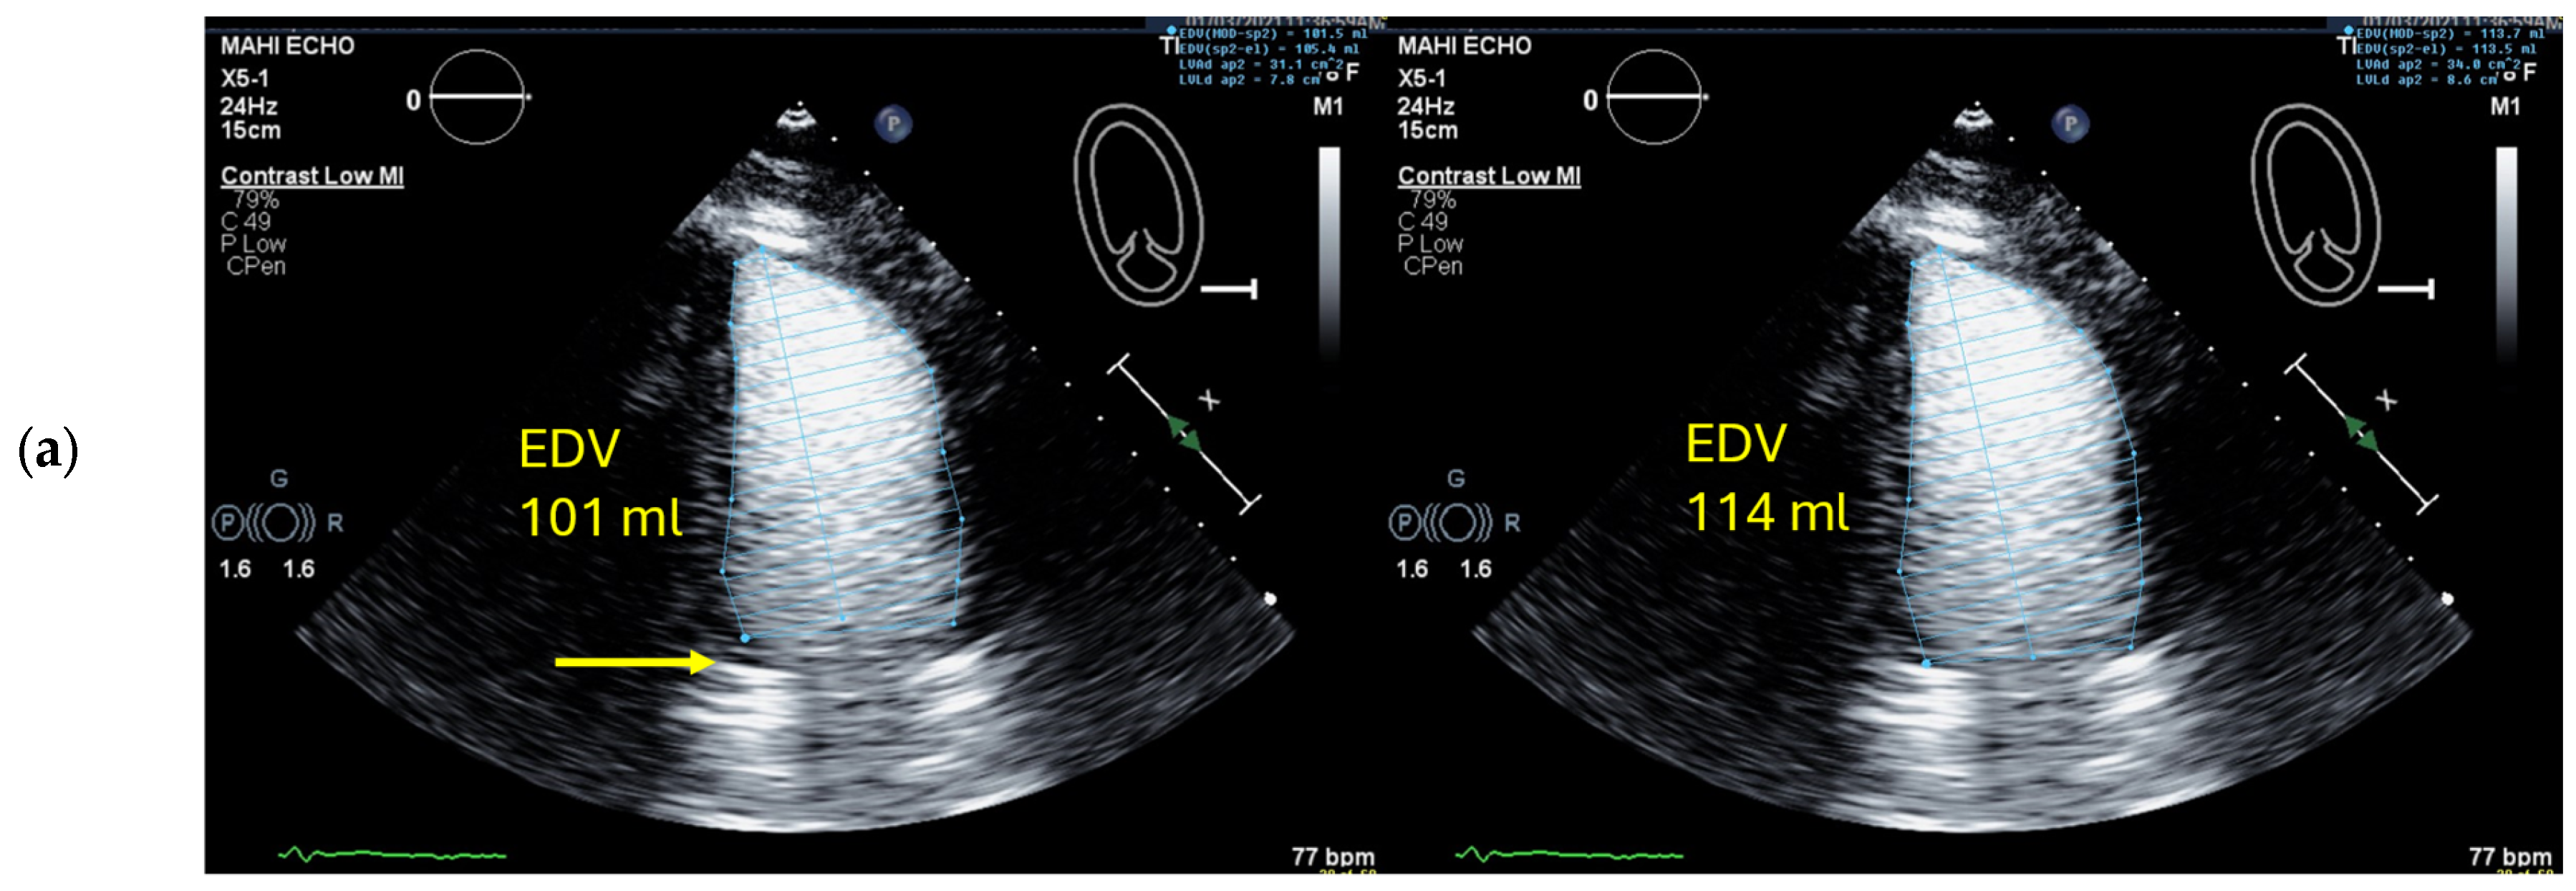

4.5. Left Ventricular Volume and Ejection Fraction Measurements

4.5.1. Pitfalls

Selection of Foreshortened Loops

| 1 | Select unforeshortened loops avoid 4-chamber views, which include anterolateral papillary muscles | When several loops are available, select the one with the longest long axis which impairs tracing of the lateral LV wall |

| 2 | Select the end-diastolic frame | The first frame after mitral valve closure or the largest LV cavity |

| 3 | Trace the LV border: end diastole | Starting on the septal mitral ring (4-chamber view) and inferior mitral ring (2-chamber view), following the dark/bright interface until the lateral/anterior mitral ring The start and end points of the contour at the mitral ring should be connected by a straight line TIP The mitral leaflets may be obscured by the UEA. Then look for the bright signals of the mitral ring, which are more clearly delineated and follow the entire loop rather than only in the end-diastolic frame. |

| 4 | Select the end-systolic frame | Smallest cavity—the mitral valve closure may be obscured by the UEA! TIP: When scrolling through the systolic frames of the loop, look for the frame when the cavity becomes larger. The frame before it is the end-systolic frame. |

| 5 | Trace the LV border: end systole | Starting on the septal mitral ring (4-chamber view) and inferior mitral ring (2-chamber view), following the dark/bright interface until the lateral/anterior mitral ring The start and end points of the contour at the mitral ring should be connected with a straight line |

| 6 | Check the LV length (distance between the middle of the line connecting the mitral ring and the apex) | When the difference in diastolic LV length between 4- and 2-chamber views is <0.5 cm, no major foreshortening can be assumed When the difference is >5 mm, the recording of the view with the shorter LV length is probably not optimal. The other recordings of this view should be reviewed to find the one with the longest LV [59]. |